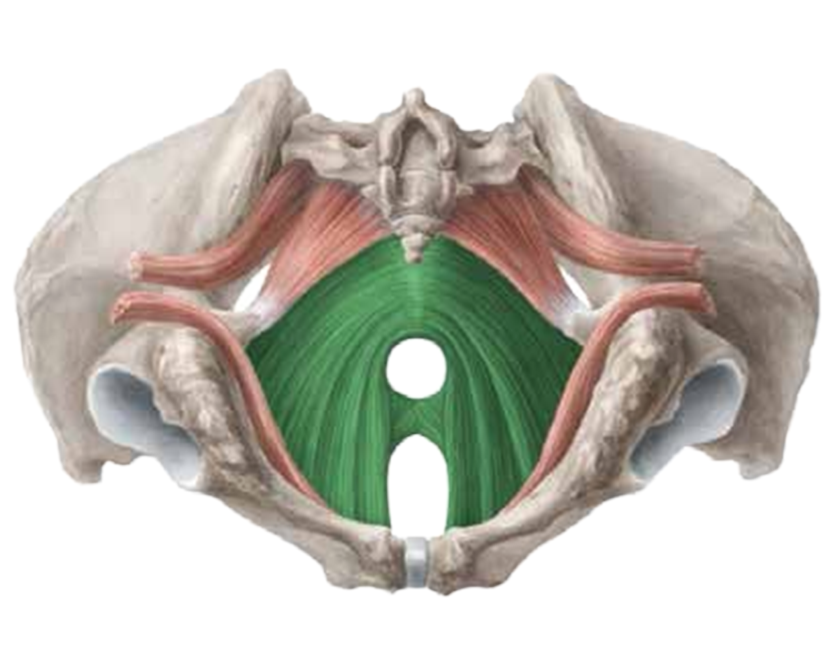

Ein funktionaler Beckenboden hat eine zentrale Rolle für die Stabilität der unteren Lendenwirbelsäule und verhilft zu einer besseren Körperhaltung. Zu schwache oder verkrampfte Gesäßmuskeln können Schmerzen verursachen, da durch diese viele Nerven (u.a. der Ischiasnerv) durchziehen und komprimiert werden können.

Der Beckenboden als Teil der (Rumpf)Stabilität hat einen wesentlichen Einfluss auf die Leistungsfähigkeit und Effizienz des gesamten Bewegungs- und Halteapparats. Das Verletzungsrisiko wird gesenkt

Mittels modernster Magnetfeldtechnologie aktiviert, stimuliert und kräftigt der PelviPower-Stuhl die Strukturen des Beckenbodens. Um eine Stärkung bis in die tiefsten Muskelschichten zu erzielen, lösen die Magnetfeldimpulse bis zu 25000 Kontraktionen aus und trainieren so gezielt Ihren Beckenboden. Die Eindringtiefe beträgt je nach gewählter Intensität 5 bis ca. 15 cm. Der Wirkfelddurchmesser beträgt bis zu 40 cm.

Der Beckenboden ist das Kraftzentrum des Körpers - die Basis - ein wesentlicher Teil der Körpermitte. Ein trainierter, starker Beckenboden hilft dabei, vielen Beschwerden wie Blasenschwäche und Inkontinenz vorzubeugen und/oder in den Griff zu bekommen. Darüber hinaus wird die Libido und sexuelle Empfindungsfähigkeit gestärkt. Rückenbeschwerden werden gemindert, die körperliche Spannkraft, Haltung, allgemeine Fitness und Vitalität verbessert.